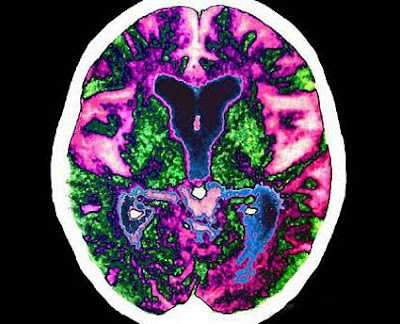

La pérdida paulatina de la memoria y la identidad, una pesadilla que cada

vez viven más ancianos. Foto: Peter Granser

Esta enfermedad, para la que no hay tratamiento eficaz, es un trastorno neurodegenerativo que se manifiesta en un deterioro de las capacidades cognitivas y alteraciones de conducta. Según la Organización mundial de la Salud (OMS), el 0,37% de la población mundial padecía demencia en 2005; se estima que este porcentaje aumente hasta un 0,44% en 2015 y un 0,55% en 2030, a medida que vaya envejeciendo la población.

Dos de los genes (llamados CLU y PICALM) han sido identificados por el equipo británico y el tercero (CR1), por los franceses. Del CLU se conocía ya su propiedad protectora del cerebro y, al igual que el APOE, le ayuda a eliminar amiloides, proteínas cuya acumulación es destructiva.

La novedad es que, según esta investigación, el gen también ayuda a reducir las inflamaciones dañinas en el cerebro causadas por una excesiva respuesta del sistema inmunológico, función que comparte con el CR1.

Los científicos consideran que la inflamación cerebral puede jugar un papel mucho más importante en el desarrollo del Alzheimer de lo que se pensaba hasta ahora, por lo que estos genes abrirían la puerta a nuevos tratamientos farmacológicos eficaces.

El gen PICALM está relacionado con el transporte neuronal de moléculas y las sinapsis (conexiones entre neuronas), ayudando a formar la memoria del individuo.